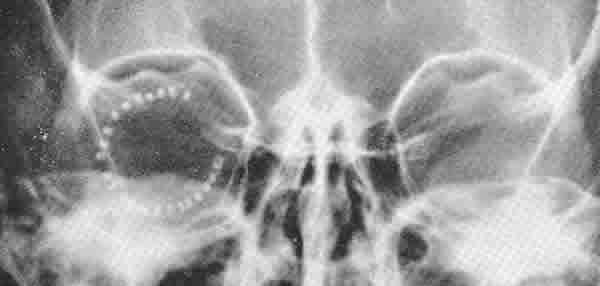

En dacriología aportó su propio trépano a motor para las osteotomías de la dacriocistorrinostomía, sus dilatadores canaliculares calibrables, y sus conformadores de seda para las vías lacrimales (30,37). En cirugía de la catarata introdujo un método de extracción del cristalino por succión, un crioextractor, y diversas otras contribuciones (7,12,37,43,45). En glaucoma hizo diversas aportaciones histopatológicas, y contribuyó con diversas variantes quirúrgicas personales (7,9,21,23). En los desprendimientos de retina introdujo el acortamiento del ojo por pliegue hacia fuera de la esclera mantenido con clips de titanio (fig. 9) (46). Para la cirugía del estrabismo diseñó un instrumento que combinaba las funciones de tres instrumentos: gancho muscular, abrazadera y compás, fabricado por E. B. Meyrowitz Inc, de Nueva York (31). En la cirugía de los párpados también hizo modificaciones para la corrección del entropión espástico senil (Ann Ophthalmol 1974; 6: 171-173), y para la corrección de la ptosis (Ann Ophthalmol 1974; 6: 163-166). Enucleaciones, orbitocirugías o cualquier tipo de operación eran tratados con sus continuas mejoras personales y con su habilidad quirúrgica. Él decía: «Cuando estás operando tu consciente y subconsciente especulan sobre lo que debes o no hacer y con qué; aciertas o no. Es más tarde, cuando estás conduciendo tu coche, cuando de pronto descubres qué es lo que deberás hacer y con qué instrumento la próxima vez».

Fig. 9. Acortamiento escleral por plegamiento externo con clips. A. Plegamiento escleral sin implicar la coroides. B. Aspecto externo. C. Aspecto radiográfico de un caso que se extiende a tres cuadrantes.